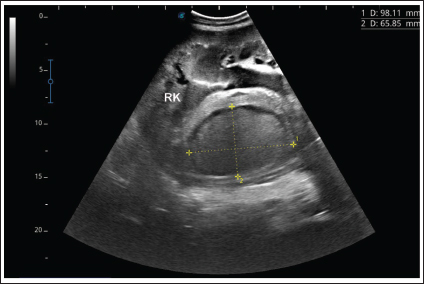

Single or multiple renal abscesses were visualized sonographically compressing the renal parenchyma. Three abscesses measuring 5.2–15.0 cm were scanned in 2 camels (11.8%); one affected the left and the other affected the right kidneys. In addition, 2 abscesses were imaged in 2 camels; both affected the left kidney. However, single abscesses measuring 3.6–14.0 cm in length were recorded in the remaining 13 camels; 9 in the right and 4 in the left kidneys. The contents of the abscesses were hyperechogenic in 8 cases (47.1%), hypoechoic in 4 (23.5%), isoechoic with hyperechoic foci in 3 cases (17.6%), and heterogenous in 2 (11.8%). In 4 of the diseased camels (23.5%), hyperechoic urine together with echogenic deposits was found within the urinary bladder (Fig. 6 and Fig. 10). Overall, unilateral lesions were found in the right kidneys only in 9 cases (52.9%) and in the left kidneys only in 6 cases (35.3%), while bilateral affection of both kidneys was found in 2 cases (11.7%). In the control camels, both kidneys appeared subjectively normal with no detectable lesions.

Ultrasonographic findings in camel number 9 with right kidney abscesses are shown in Figure 7, where the lesion appeared compressing the parenchyma of the right kidney. Its contents are hyperechoic, and its capsule is thick. Figure 8 shows sonographic findings in camel number 11 with abscessation of the right and left kidneys. Abscesses measured 7.6 × 6.9 cm and 9.3 × 8.1 cm with isoechoic contents. A third abscess in the same camel was found within the left kidney. It was relatively large and was isoechoic. Ultrasonographic findings in camels 15 and 16 with abscesses of the left kidney are shown in Figure 9. A large abscess was found in camel number 15 with isoechoic contents and a thick capsule, while a small abscess was imaged in the left kidney of animal number 16 with heterogeneous contents. Figure 10 shows the ultrasonographic findings in camel number 17 with abscessation of the left kidney. A large abscess was found compressing the parenchyma of the left kidney with isoechoic contents. The urinary bladder in the same camel contained echogenic deposits that appeared to be highly echogenic.

Fig. 7. Ultrasonographic findings in camel number 9 with abscessation of the right kidney-. The lesion appeared to compress the parenchyma of the right kidney (RK), its contents are hyperechoic, and its capsule is thick.